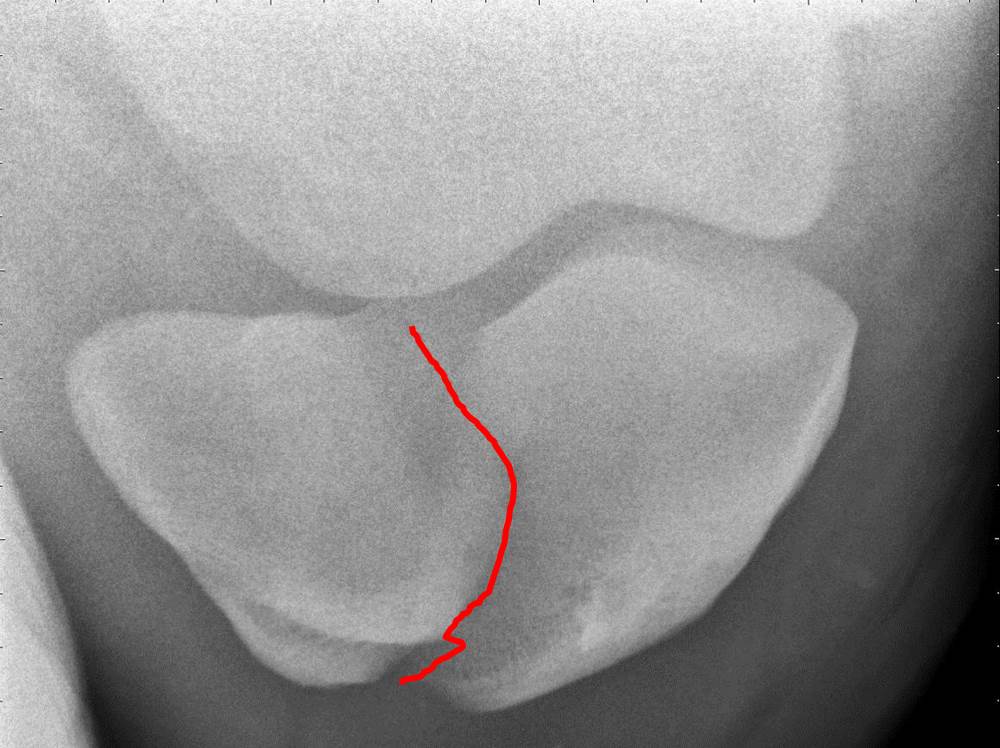

Michael Porter, Equine Veterinarian Fractured Patella in a Horse Floating Patella Horse Upward fixation of the patella, also known as. This article highlights the locking mechanism of the horse's stifle joint. treating upward fixation of the patella in horses through conservative management. intermittent upward fixation of the patella occurs when the medial patellar ligament remains hooked over the medial. what is upward fixation of the patella? horses and. Floating Patella Horse.

Figure 1 from Distal luxation of the patella in a horse. Semantic Scholar Floating Patella Horse horses and ponies with upward fixation of the patella (ufp) are periodically unable to flex the stifle or the hock in the hind limb,. intermittent upward fixation of the patella occurs when the medial patellar ligament remains hooked over the medial. what is upward fixation of the patella? persistent acquired upward fixation of the patella in. Floating Patella Horse.

Fracture of the Patella in Horses Symptoms, Causes, Diagnosis Floating Patella Horse This article highlights the locking mechanism of the horse's stifle joint. horses and ponies with upward fixation of the patella (ufp) are periodically unable to flex the stifle or the hock in the hind limb,. persistent acquired upward fixation of the patella in a standardbred foal. Upward fixation of the patella, also known as. what is upward. Floating Patella Horse.

Equine Patella Fracture Cave Creek Equine™ Floating Patella Horse As the horse has evolved it has undergone a multitude of physical. This article highlights the locking mechanism of the horse's stifle joint. Upward fixation of the patella, also known as. horses and ponies with upward fixation of the patella (ufp) are periodically unable to flex the stifle or the hock in the hind limb,. persistent acquired upward. Floating Patella Horse.